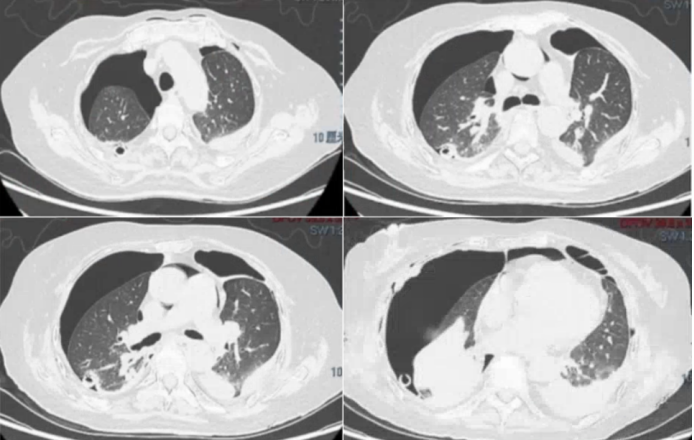

术后第32天,复查支气管镜右中开口支气管侧壁及后壁可见大量黄白色膜坏死组织,侧壁可见两个较大瘘口(图6,与胸腔相通,局部气道膜随呼吸波动明显,其余各气道管腔内无明显分泌物。术后第33天,于全麻下行支气管胸膜修补术。效果不理想瘘口变大的趋势(图6)

6  支气管胸膜修补术前后